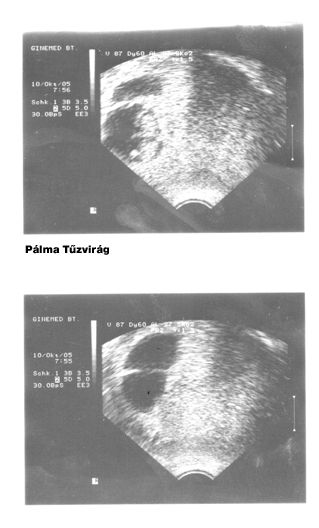

És íme a legelső UH-fotók a babákról:

Vadvirág